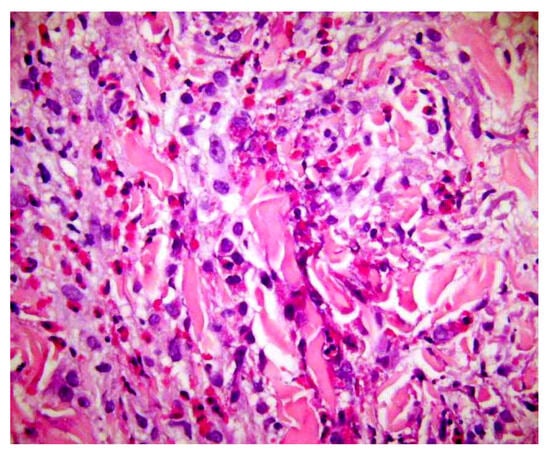

Examples include abundant mucin in the reticular dermis, acantholytic dyskeratotic cells within a cleft, flame figures, sarcoidal granulomas, or eosinophilic abscesses. None of these features is pathognomonic: each may occur in several unrelated entities. Yet, when observed, they stimulate the diagnostician to select a set of plausible hypotheses, deduce the additional features that should accompany each hypothesis, and test them through further histologic levels, special stains, or clinicopathologic correlation (Figure 8).

Figure 8.

Flame figures: degenerated dermal collagen bundles coated with eosinophilic granules, which give them a bright red color resembling a flame. Though characteristically described in Wells’ syndrome, they are not pathognomonic of this disease, but can be encountered in any condition with numerous eosinophils, including bullous pemphigoid, insect bite reaction, scabies, eosinophilic folliculitis, drug reactions, mycotic infections.

Within this Select-and-Test (ST) framework, such indeterminate clues serve as vehicles for abductive reasoning. They generate weak abductions—tentative, exploratory explanations that define a hypothesis space rather than a conclusion. For instance, identifying eosinophilic abscesses may raise competing hypotheses such as Wells’ syndrome, eosinophilic folliculitis, or a drug reaction. Abduction organizes this uncertainty: the observer asks, “What else should I see if this is Wells’ syndrome? Is there flame-figure formation, collagen degeneration, or a peripheral eosinophilia?” Deductive prediction and empirical testing then refine or overturn the initial guess.